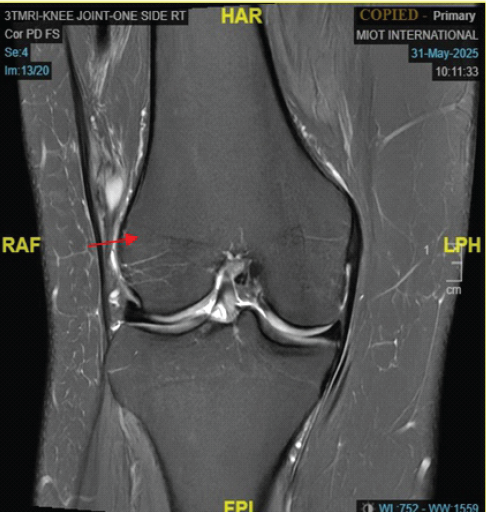

Synovial Sarcoma Disguised as a Ganglion Cyst in a Patient with Chronic Knee Pain

Ashok Selvaraj , Akilesh Kumar , Robin G Alex , Senthil Narayanan

………………………………p.114-119